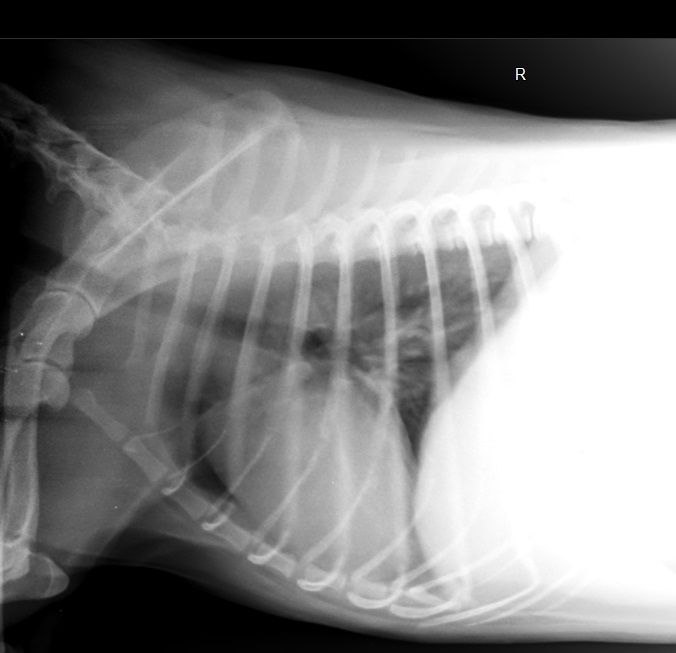

Рентгенография — один из самых точных методов диагностики. Она необходим при:

- Травмах и подозрении на переломы — особенно после падения или аварии;

- Проблемах с дыханием — чтобы исключить пневмонию, инородное тело или плеврит;

- Болях в спине или хромоте — для выявления грыж, артритов, дисплазий;

- Завороте кишок или непроходимости — особенно у собак крупных пород;

- Контроле лечения — например, срастание костей после операции.

- Съемка: делается 1–3 снимка с разных ракурсов.

- Расшифровка: врач-рентгенолог анализирует снимки и готовит заключение.